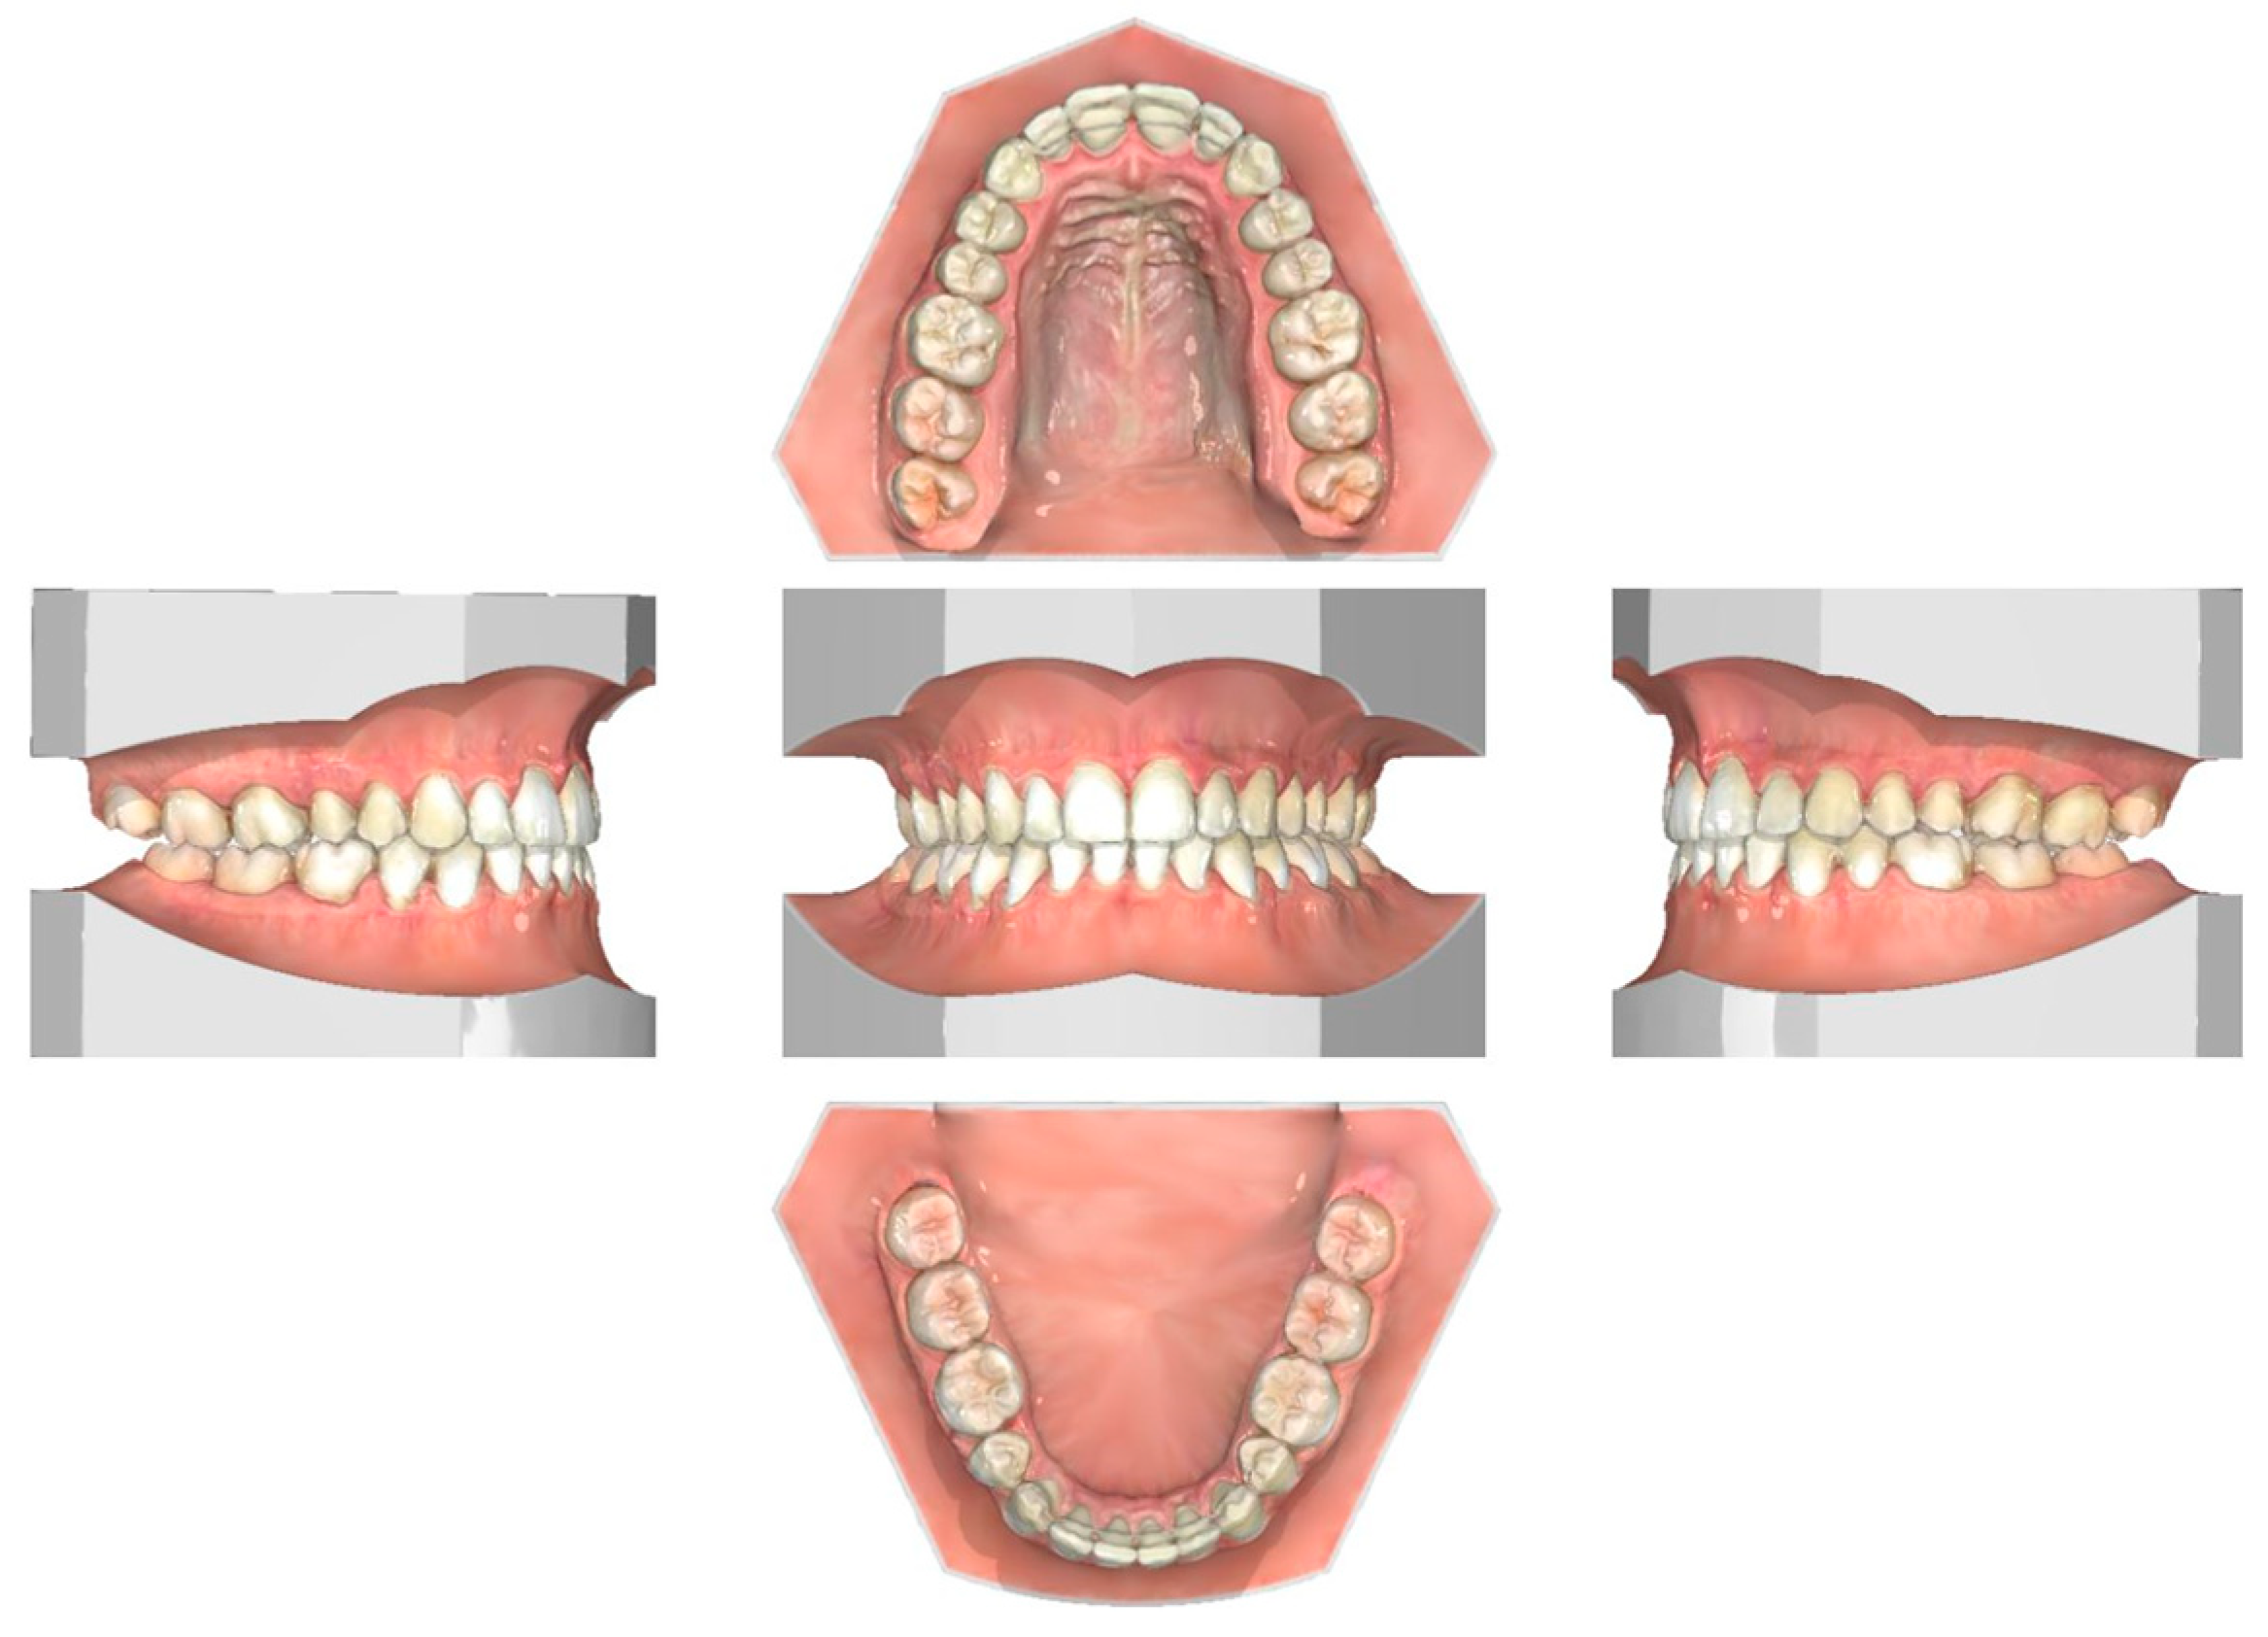

2.1. Diagnosis and Individual Treatment Planning

2.2. Clinical Preparations